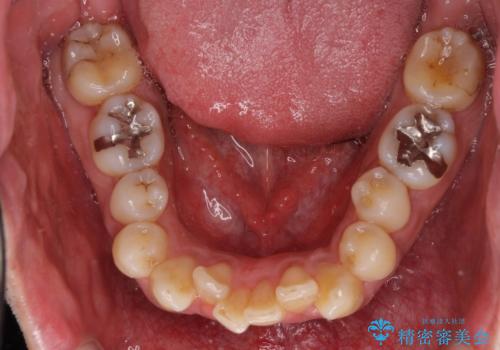

- 上下前歯のデコボコを気にして来院された患者様です。

下顎骨が顕著な左右差を持って成長したため、右側にずれている状態でした。

デコボコは抜歯をすることなく解消できる程度であったため、インビザラインにより矯正治療を行うこととしました。